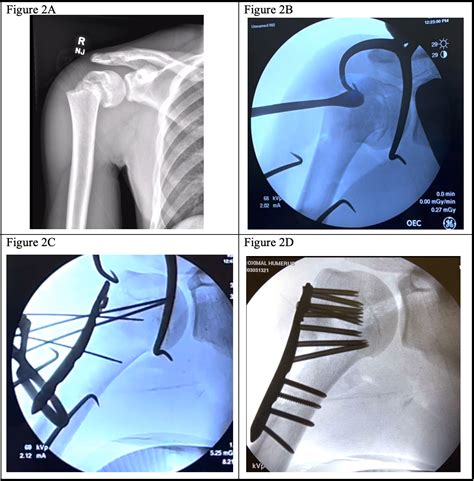

For more severe fractures, surgery may be necessary to realign the bone and promote healing. Surgical options include:

• Open Reduction and Internal Fixation (ORIF): A procedure where the fracture is surgically realigned and stabilized using plates, screws, or pins.

Case Study 2: Mr. Johnson, 45 Years Old

Mr. Johnson, a 45-year-old construction worker, fell from a ladder and sustained a complex proximal humerus fracture. He underwent open reduction and internal fixation (ORIF) to realign the bone and stabilize the fracture. Post-operative physical therapy was crucial for his recovery, and he returned to work within three months.